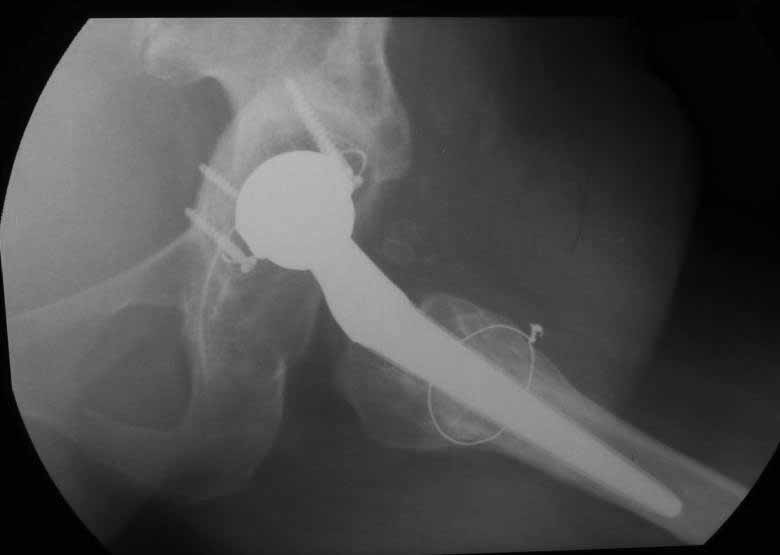

Уважаемые коллеги. Хотелось бы услышать мнения и советы по представляемому случаю. Пациентка 45 лет. Бесцементное эндопротезирование левого тазобедренного сустава 6 лет назад (впадина RM, Mathys, металл-металл, ножка Зульцеровская). За 10 лет до протезирования – коррегирующая остеотомия бедренной кости, которая не срослась в течение года до удаления пластины, а затем срослась в течение 3 месяцев иммобилизации в кокситной повязке. После протезирования получилось наблюдать пациентку почти постоянно, поскольку через 2 года синтезировал ей лодыжки на оперированной стороне, затем, через несколько месяцев удалил фиксаторы, а в 2009г. резецировал мениск на противоположной стороне. Боли все эти годы не беспокоили. Пациентка чуть выше среднего роста, вес тела нормальный. Физические нагрузки переносила хорошо. Работает на 7 этаже без лифта. Год назад экстирпация матки по поводу лейомиомы больших размеров. Несколько месяцев назад появились боли в области левого тазобедренного сустава. При рентгеновском и КТ исследованиях (июль с.г.) – нестабильность тазового компонента. От предложенной замены протеза пациентка на тот момент, слава богу, отказалась. Через какое то время боли в области левого тазобедренного сустава практически полностью прошли, а около 2 месяцев назад появилось ощущение патологической подвижности таза и боли в паху справа, которые через некоторое время уменьшились, а потом снова усилились после значительных физических нагрузок (много ходила по песку на пляже, носила тяжести). Ежедневно принимала диклофенак. На рентгенограммах – переломы правой лонной кости. Сейчас госпитализирована из-за болей в паху справа. Боли слева не беспокоят. На фоне снижения нагрузок в стационаре боли значимо уменьшились. Способна ходить без средств дополнительной опоры.В анализах крови чуть повышены трансаминазы и гамма-ГТ, моча без особенностей.

Вопросы: -правильно ли я расцениваю переломы как стрессовые на фоне неполноценного таза (pelvic insufficiency stress fractures)? -Можно ли так же расценить ситуацию на стороне протеза и, соответственно, не торопиться с ревизией, рассчитывая на вторичную стабилизацию? Уж больно не хочется менять ножку. -Если думать о ревизии, то когда? На представленных снимках тазобедренный сустав до и сразу после операции, затем 2 снимка 2009г., когда ничего не беспокоило, затем КТ 2-х месячной давности и вчерашние рентгенограммы обоих тазобедренных суставов.

Сергей, очень возможно, что перелом и стрессовый, но мне видится, что его причина в нестабильности чашки. Дело в том, что в отличии от ножек, чашка при своей дестабилизации болит гораздо меньше и больные терпят до последнего.

При сравнении рентгенограмм можно увидеть насколько чашка переместилась от места своего первичного расположения. От опрокидывания ее удерживают конструкционные элементы "рожки". Без них ситуация, возможно, уже была бы катастрофической (чашка в тазу). Думаю надежды на вторичную интеграцию, могут быть обмануты и ревизии не избежать.

Если внимательно посмотреть на рентгеновские снимки, то видно, что пара трения действительно металл-металл.